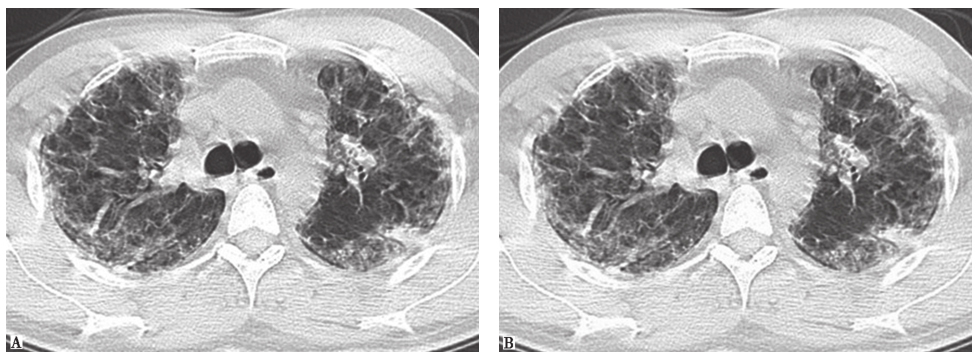

过敏性肺炎(HP):也称外源性过敏性肺泡炎(EAA),指易感个体反复吸入有机粉尘抗原后诱发的肺部变态反应性疾病。急性HP胸部HRCT表现为大片状或斑片性磨玻璃和气腔实变阴影,内有弥漫性分布且边界难以区分的肺腺泡性小结节影(图8),直径<5mm,伴小叶中心和细支气管周围分布,斑片性磨玻璃样变和肺泡过度充气交错形成马赛克征象。亚急性HP胸部HRCT主要显示沿小叶中心和细支气管周围弥漫分布的边界不清的小结节影;细支气管炎可导致支气管阻塞,引起气体陷闭,形成小叶分布的斑片样过度充气区(图9)。慢性HP胸部HRCT主要表现为小叶间隔和小叶内间质不规则增厚,蜂窝肺伴牵拉性支气管或细支气管扩张和肺大疱,间或混有斑片性磨玻璃样变(图10)。根据明确的抗原接触史,典型的症状发作及其与抗原暴露的明确关系,胸部影像学表现和肺功能特征性改变,支气管肺泡灌洗检查显示淋巴细胞明显增加(通常淋巴细胞>40%, CD4+/CD8+<1),可以做出明确诊断。经支气管肺活检取得的合格病理资料可进一步支持诊断,一般不需要外科肺活检。

图9亚急性过敏性肺炎胸部CT表现

胸部CT示两肺弥漫性边界不清的小结节影

图10慢性过敏性肺炎胸部CT表现

胸部CT示两肺磨玻璃影、蜂窝肺形成